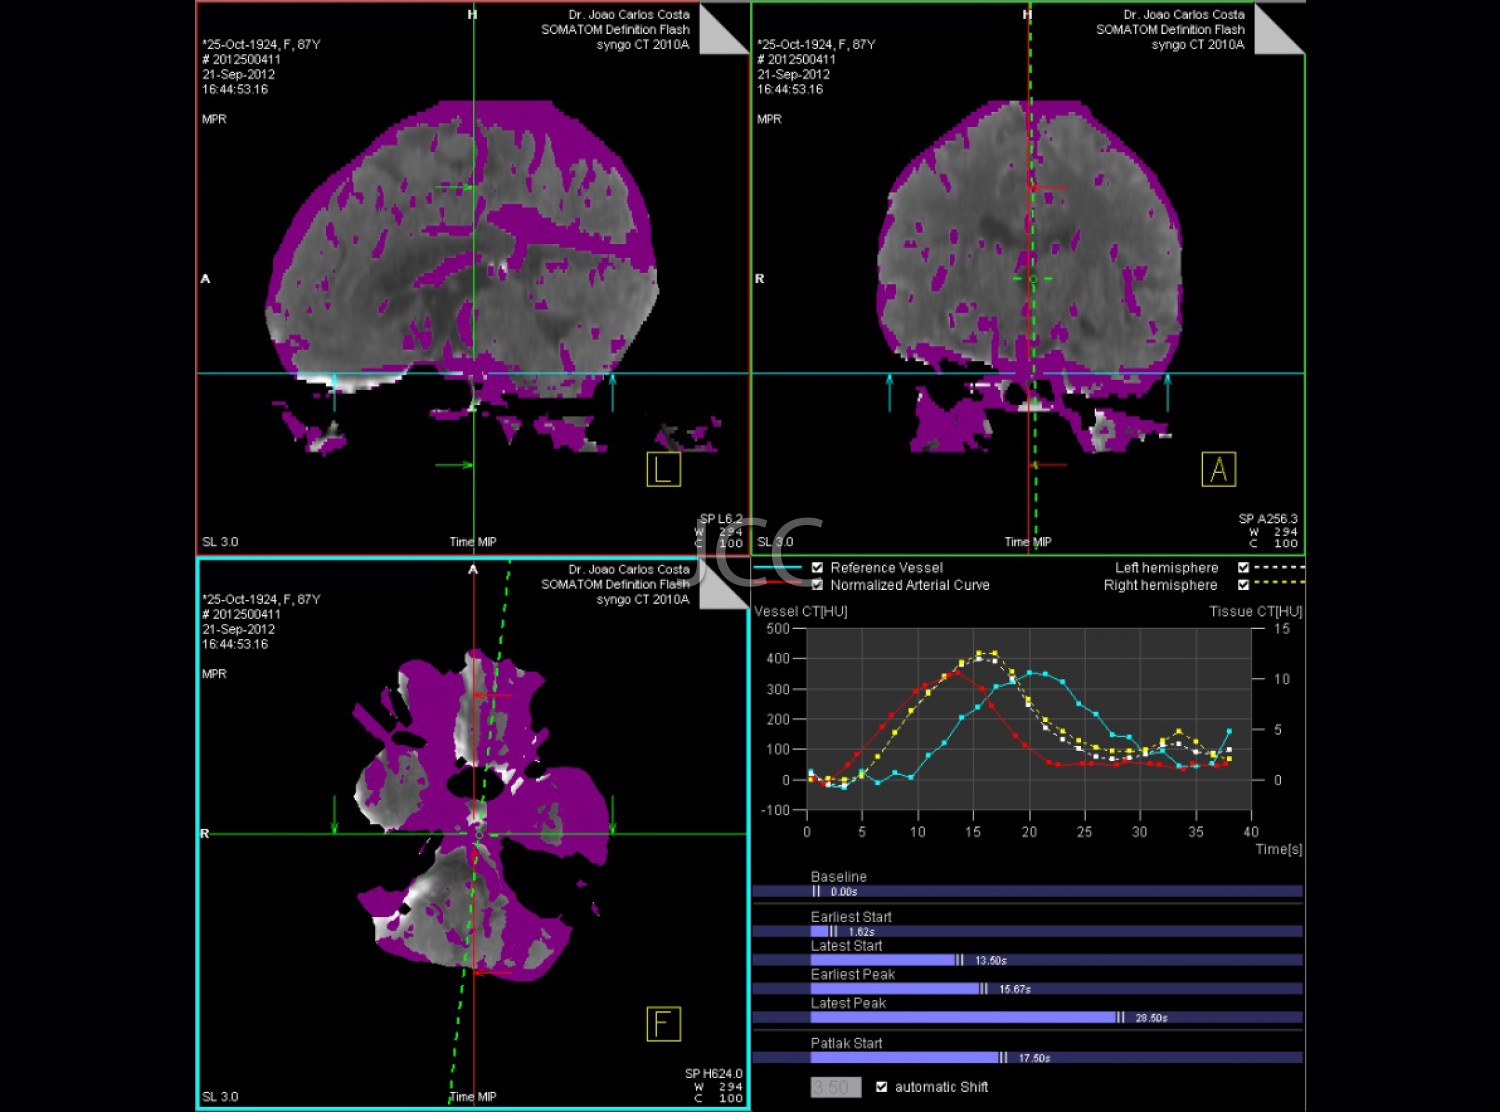

Discover here the exams available in the clinics of the Dr. João Carlos Costa Group.